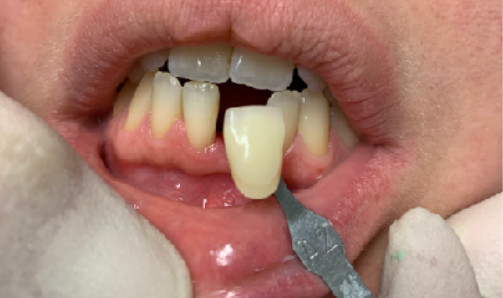

The reduced diameter of the neck allows you to protect yourself from any peri-implantitis and significantly improves the speed of healing. In this case it was tapped with a diameter of 4 and a Tramonte implant with a diameter of 4 mm with 7 threads with short neck was inserted. The titanium used is always grade 4.

| Welding: No | Dental area: lower incisor 31 |

| Extractive situation: Immediate post-extraction implant with immediate loading. | Density according to Misch: D2 |